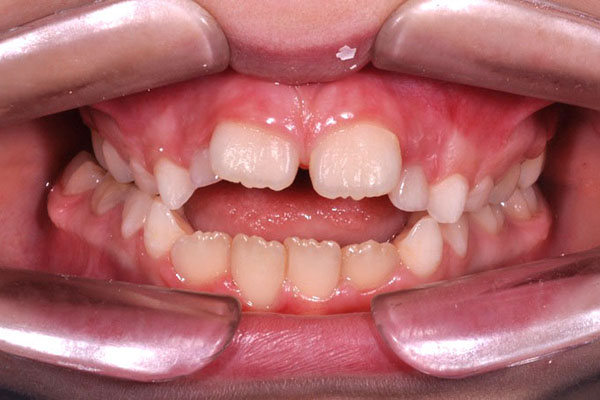

Overjet aumentato con incisivi superiori molto sporgenti (così detto aspetto del Brutto anatroccolo)

Il trattamento ortodontico nel bambino con “denti sporgenti” consente, ottimizzando il tempo di utilizzo delle apparecchiature, di ridurre il rischio di frattura traumatica dei denti anteriori, di migliorare l’estetica e di aumentare l’autostima del paziente (riducendo le conseguenze del bullismo di coetanei tipico di queste condizioni).